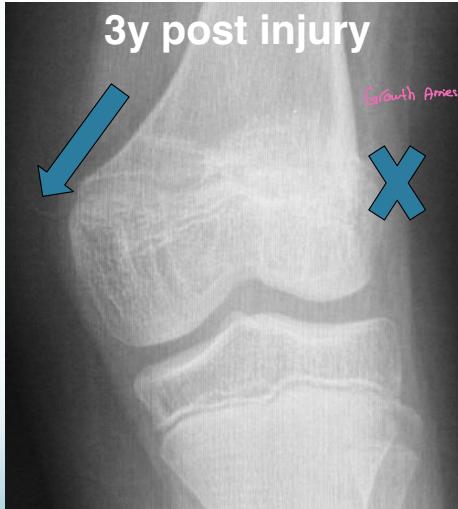

Asymmetrical Physeal Affection

- Seen on x-ray

- One side grows more than the other

- Causing an increasing deformity

- Oblique Park-Harris growth arrest/recovery line (white arrows)

Case Example: 12-year-old male, Salter-Harris Type II